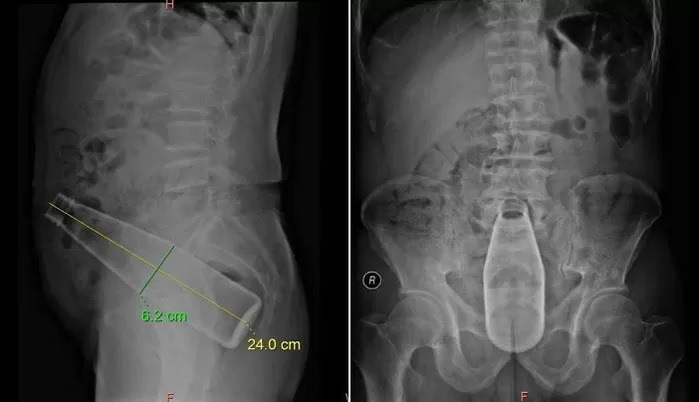

똥꼬맞아?

어떻게 저게 들어가냐??